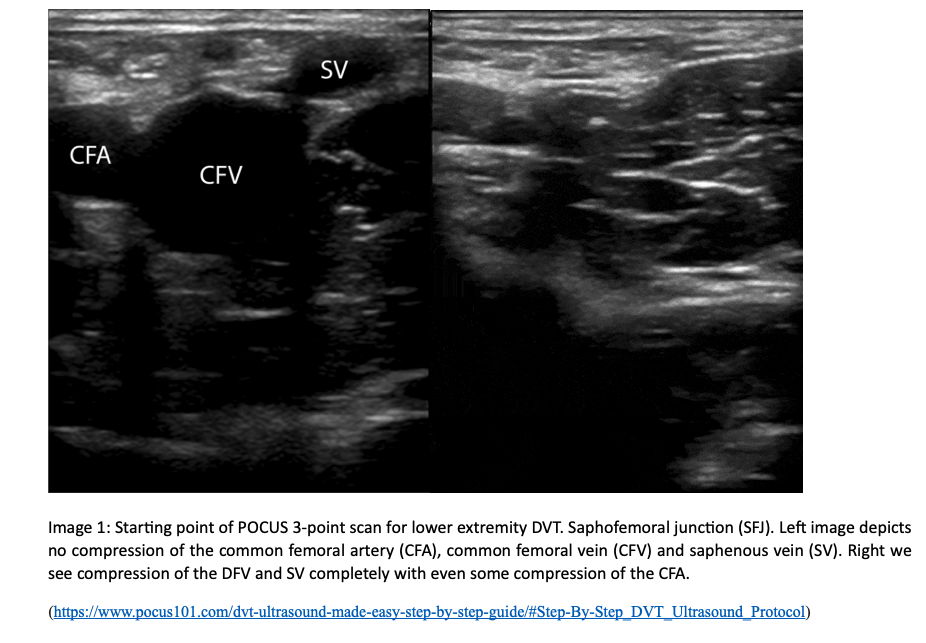

1. The most proximal point of our POCUS is the saphenofemoral junction (SFJ).  For the first point of the scan, patient should be supine with the patient’s leg externally rotated and the knee flexed in a “frog-leg” position. Place the linear transducer transversely over the inguinal crease. The probe should be perpendicular to the skin with the indicator facing the patient’s right. Find the common femoral artery and common femoral vein (CFV). Proximal to the common femoral artery and vein, locate the SFJ as your most proximal point, which is 1-2 cm below the inguinal canal combining with the CFV.

2. Continue to scan distally to locate where the CFV branches into the deep femoral vein and the femoral vein (previously known as superficial femoral vein). Remember the CFV will be medial to the common femoral artery. Compress the femoral vein distal to the bifurcation of the CFV at the SFJ. I like to compress until I cannot visualize anymore and the vasculature dives into the adductor canal.  Firmly compress the ultrasound probe to assess if the vein compresses entirely.